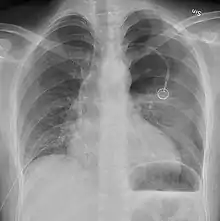

Not all pneumothoraces are uniform; some only form a pocket of air in a particular place in the chest.[14] Small amounts of fluid may be noted on the chest X-ray (hydropneumothorax); this may be blood (hemopneumothorax).[13] In some cases, the only significant abnormality may be the "deep sulcus sign", in which the normally small space between the chest wall and the diaphragm appears enlarged due to the abnormal presence of fluid.[15]

Anteroposterior expired X-ray at the same time, more clearly showing the pneumothorax in this case